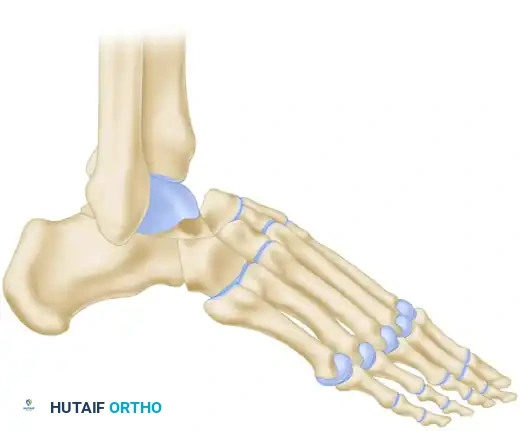

Triple arthrodesis is a powerful, time-honored orthopedic procedure designed to fuse the three primary joints of the hindfoot and midfoot: the subtalar (talocalcaneal), talonavicular, and calcaneocuboid joints. Historically conceptualized to manage the devastating sequelae of poliomyelitis, the procedure has evolved significantly. Today, it remains the gold standard for addressing severe, rigid, and painful deformities of the hindfoot that are refractory to conservative management and joint-sparing osteotomies.

The hindfoot functions as a complex, interdependent unit. The subtalar joint primarily accommodates inversion and eversion, allowing the foot to adapt to uneven terrain. The talonavicular and calcaneocuboid joints (Chopart's joint) dictate the flexibility of the midfoot. When the subtalar joint is everted, the axes of the talonavicular and calcaneocuboid joints are parallel, unlocking the midfoot for shock absorption. Conversely, during inversion, these axes diverge, locking the midfoot to provide a rigid lever arm for toe-off.